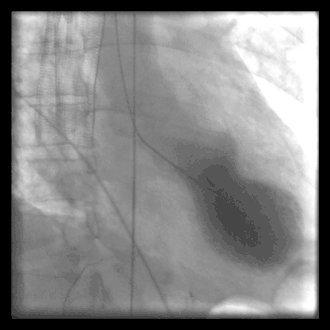

A common example of cardiac catheterization is coronary catheterization that involves catheterization of the coronary arteries for coronary artery disease and myocardial infarctions ("heart attacks"). Catheterization is most often performed in special laboratories with fluoroscopy and highly maneuverable tables. These "cath labs" are often equipped with cabinets of catheters, stents, balloons, etc. of various sizes to increase efficiency. Monitors show the fluoroscopy imaging, electrocardiogram (ECG), pressure waves, and more.

A patient undergoing a procedure where an 8 F introducer was placed in the right internal jugular vein using a 5F MAK access kit. A 7 F balloon tipped catheter was introduced via the venous sheath, the balloon was inflated and the catheter was advanced through the right heart chambers into the pulmonary capillary wedge position. Right sided pressures were obtained and cardiac output was measured using thermodilution.

A person undergoing a procedure where an 8 F introducer was placed in the right jugular vein using a 5F MAK access kit. A 7 F balloon tipped catheter was introduced via the venous sheath, the balloon was inflated and the catheter was advanced through the right heart chambers into the pulmonary capillary wedge position. Right sided pressures were obtained and cardiac output was measured using thermodilution.